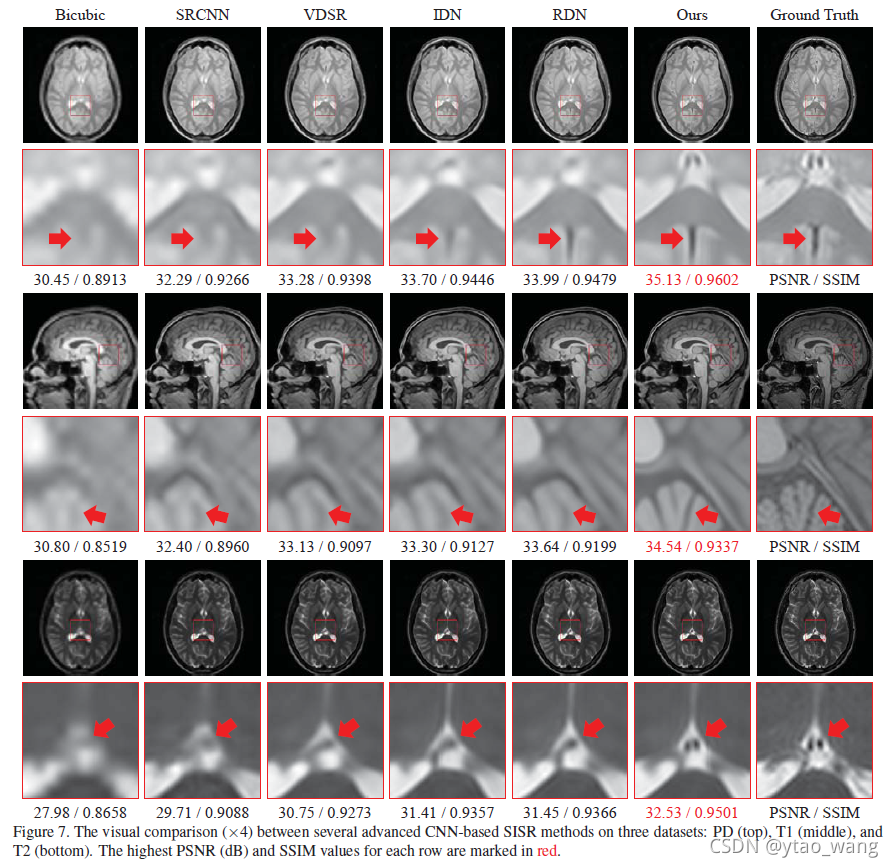

4.4.2 可视化对比

图7显示了Tab中比较方法的视觉效果。如图3所示,在三个数据集上:分别具有比例因子×4的PD(顶部),T1(中间)和T2(底部)图像。可以看出,所提出的SERAN模型在所有图像类型上显示出优于其他方法的显着可见优势。例如,在PD图像中,有一个由红色箭头指示的黑色区域。Bicubic,SRCNN[8],甚至VDSR[18]的结果几乎完全丧失了这种结构。虽然可以在IDN[15]和RDN[48]的结果中观察到,但我们的模型提供了更清晰的指示和更好的地面实况近似。从T1和T2图像的结果也可以观察到类似的比较,这说明了我们提出的模型在MR图像超分辨率任务中的优越性。